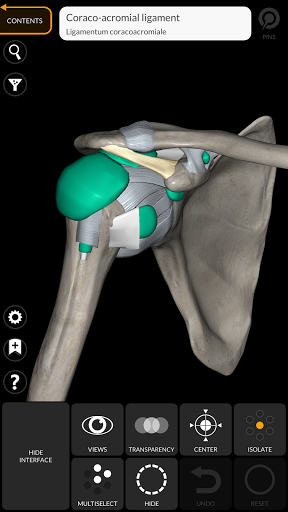

"Anatomía - Atlas 3D" permite estudiar la anatomía humana de forma fácil e interactiva.

A través de una interfaz sencilla e intuitiva es posible observar cada estructura anatómica desde cualquier ángulo.

Los modelos anatómicos 3D son especialmente detallados y con texturas de hasta una resolución de 4k.

La subdivisión por regiones y las vistas predefinidas facilitan la observación y el estudio de partes individuales o grupos de sistemas y las relaciones entre los diferentes órganos.

• Sistema musculoesquelético

nervioso • Sistema respiratorio • Sistema digestivo • Sistema urogenital (masculino y femenino) • Sistema endocrino • Sistema linfático • Sistema ocular y auditivo CARACTERÍSTICAS • Interfaz sencilla e intuitiva • Rotar y hacer zoom en cada modelo en el espacio 3D • Opción para ocultar o aislar uno o varios modelos seleccionados • Filtro para ocultar o mostrar cada sistema • Función de búsqueda para encontrar fácilmente cada parte anatómica • Función de marcador para guardar vistas personalizadas • Rotación inteligente que mueve el centro de rotación automáticamente • Función de transparencia • Visualización de músculos a través de niveles de capas desde las superficiales hasta las más profundas • Al seleccionar un modelo o un pin, aparece el término anatómico relacionado • Descripción de los músculos: origen, inserción, inervación y acción • Mostrar/ocultar interfaz de usuario (muy útil con pantallas pequeñas) MULTILINGÜE • Los términos anatómicos y la interfaz de usuario están disponibles en 11 idiomas: latín, inglés, francés, alemán, italiano, portugués, turco, ruso, español, Chino, japonés y coreano • Los términos anatómicos se pueden mostrar en dos idiomas simultáneamente REQUISITOS DEL SISTEMA • Android 8.0 o posterior, dispositivos con al menos 3 GB de RAM Reversi

Ligamentos agregados